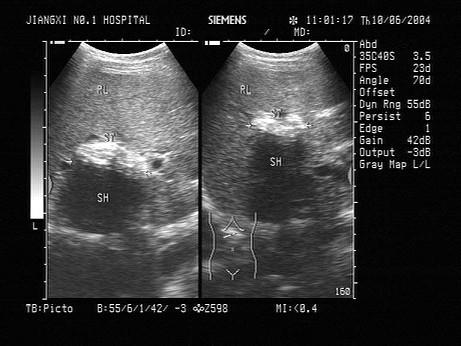

问题 男,56岁,上腹部经常剧烈疼痛不适,皮肤巩膜黄染,加重1周。声像图如图所示,诊断为?(?)

选项 A.肝内胆管蛔虫 B.肝内胆管胆汁淤积 C.肝内钙化灶 D.肝内胆管多发性结石 E.肝内血管瘤

答案 D